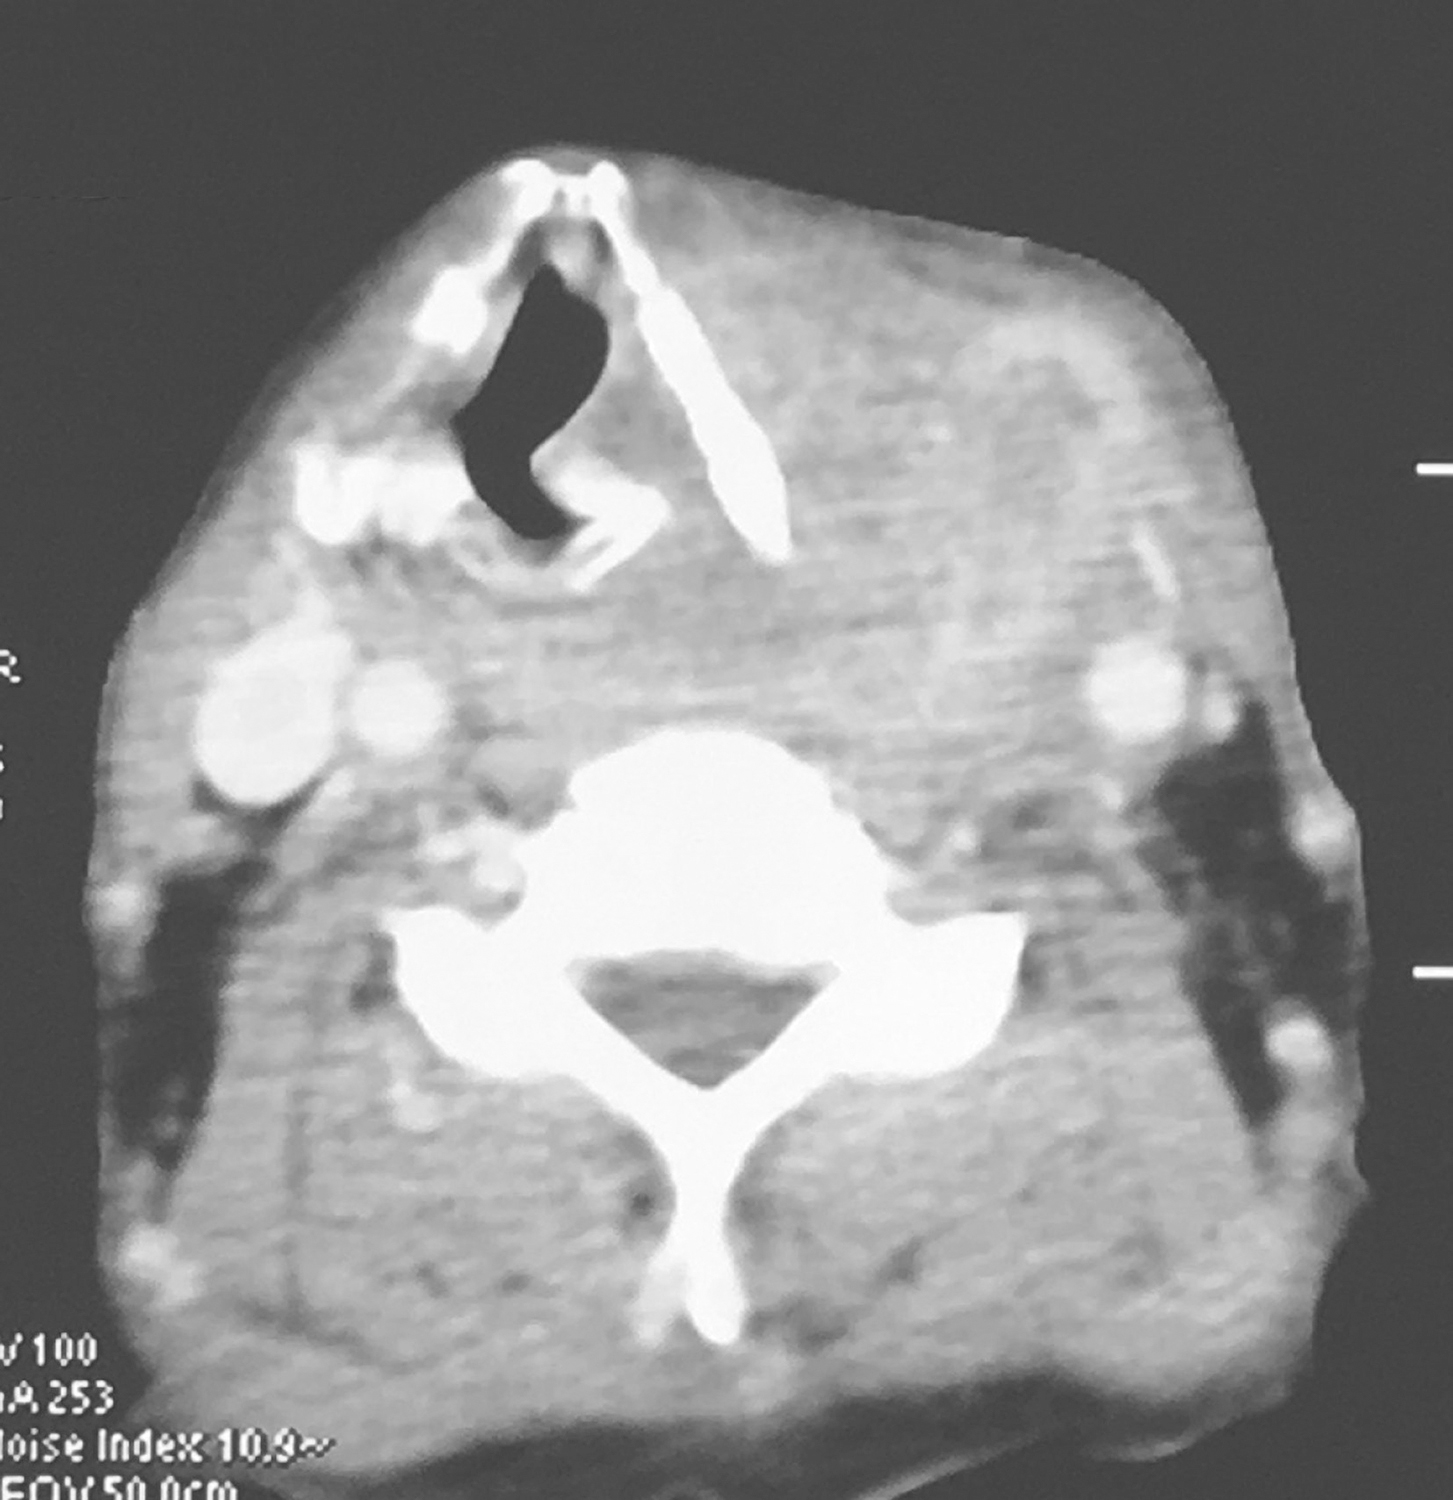

3.颈胸强化CT检查

①下咽部左梨状窝区可见软组织密度影,增强扫描可强化,向内累及左侧半喉,侵犯会厌前间隙、声门旁间隙,肿瘤侵透甲状软骨板、舌骨、累及咽侧壁及下咽后壁(图1、图2),向下累及环后区及颈段食管,向外侵犯喉外肌肉及颈前软组织。颈动脉鞘周围多枚肿大淋巴结,部分融合,边界不清,与咽喉肿瘤及颈前肌肉融合,右侧甲状腺受侵(图3),颈内静脉闭塞(图4),颈总动脉与肿瘤边界不清。右侧颈鞘周围也可见多枚肿大淋巴结,增强扫描可见强化。②双肺纹理增粗,双肺野及纵隔内未见异常。

影像学诊断:符合下咽部恶性肿瘤累及喉,双颈部多发淋巴结转移表现。

图1下咽部左梨状窝区可见软组织密度影,增强扫描可强化

图2向内累及左侧半喉,侵犯会厌前间隙、声门旁间隙,肿瘤侵透甲状软骨板、舌骨、累及咽侧壁及下咽后壁